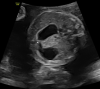

Results: In an 8-year-old boy presenting with severe aortic dilatation, facial dysmorphism, and overgrowth at birth a de novo p.Gly375Arg KCNMA1 mutation was identified which has been reported previously in association with gingival hypertrophy, aortic dilatation, and developmental delay. Additionally, in a 30-week-old fetus with severe growth retardation and duodenal atresia a de novo p.Pro805Leu KCNMA1 mutation was identified. The latter has also been reported before in a boy with severe neurological manifestations, including speech delay, developmental delay, and cerebellar dysfunction.

Conclusion: The current report presents the first antenatal presentation of a pathogenic KCNMA1 mutation and confirms the specific association of the p.Gly375Arg variant with early onset aortic root dilatation, gingival hypertrophy, and neonatal overgrowth.